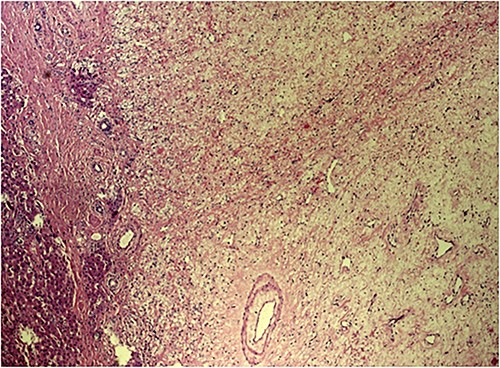

The post-operative course was uneventful, and the patient was discharged on 14th post-operative day. Pathologist’s report described a giant solid tumour without cystic component with maximum diameter of 35 cm, 8 kg weighted (Fig. 3) and clear surgical margins. Microscopic study showed a well circumscribed tumour, surrounded by an irregular margin of compressed hepatic parenchyma. Hypo-cellulated loose myxoid stroma was the almost exclusive component in the centre of the tumour, rich of blood and lymphatic vessels but small bile ducts and hepatocyte islands were nearly absent (Fig. 4). The mesenchymal component of the tumour was reactive to desmin and smooth muscle actin. Low proliferation index was confirmed (MIB1).

Grossly, MHL appears as a well-circumscribed, unencapsulated mass, whose size can vary greatly ranging from some centimetres up to >30 cm with a soft, myxoid, and cystic cut surface. They appear as solitary lesion of the right liver lobe but, multifocal cases with satellite nodules have been reported. Microscopically, there is a mixture of epithelial and stromal components where the first is mainly represented by tortuous dilated bile ducts, the second by spindle cells in a background that ranges from myxoid in ~50% of the cases, to collagenous or hyalinized in 47%. Vessels consist of small to medium sized veins or capillaries, hepatocytes are found in cords, islands, or lobules [13–15].